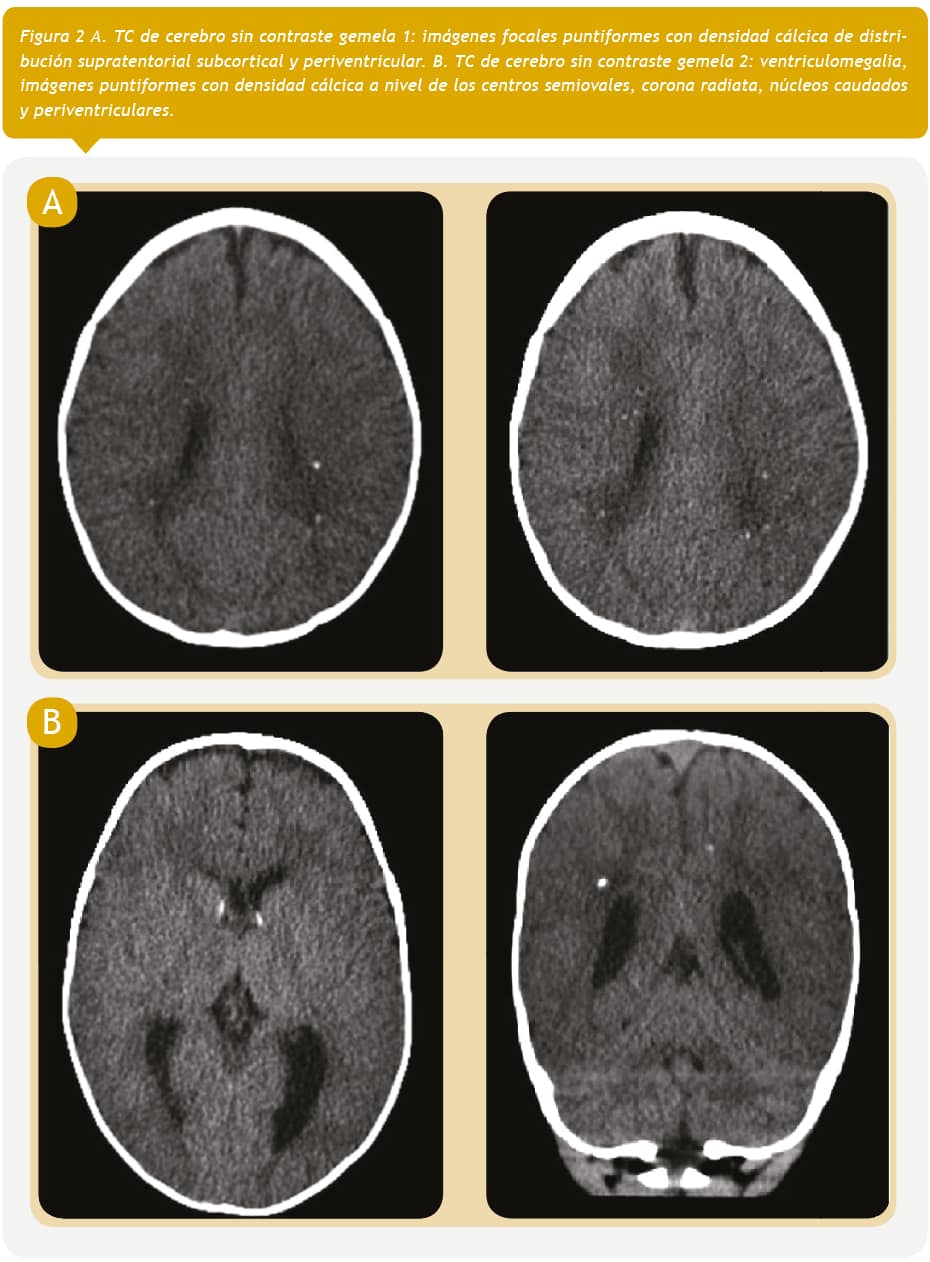

Nacieron gemelas de sexo femenino de 38 semanas de edad gestacional (Tabla 1). El examen físico al nacer fue normal. En el fondo de ojos ambas presentaron signos de coriorretinitis activa bilateral (Figura 1) y en las ecografías y TC cerebrales se detectaron calcificaciones cerebrales (Figura 2A y 2B). No se realizó RPC en sangre ni en líquido cefalorraquídeo (LCR) para toxoplasmosis. No se estudió la placenta ni la sangre de cordón umbilical. No se realizó punción lumbar para obtención de LCR debido a que el compromiso neurológico fue confirmado por la presencia de lesiones oculares y cerebrales. En base a los antecedentes maternos, resultados serológicos de ambas gemelas y hallazgos compatibles en el fondo de ojos e imágenes cerebrales, y habiéndose descartado otras infecciones que pueden producir un cuadro similar, se hizo el diagnóstico de toxoplasmosis congénita sintomática con compromiso neurológico.

Para determinar la extensión del compromiso del RN, es necesario realizar un hemograma, estudio de la función hepática, fondo de ojos e imagen del sistema nervioso central (SNC). La ecografía permite detectar lesiones de mayor tamaño en el parénquima cerebral mientras que la RM tiene mayor sensibilidad que la TC al permitir la detección de microcalcificaciones no visibles. También se recomienda realizar una punción lumbar con estudio citoquímico del LCR donde puede detectarse un aumento del nivel de proteínas7. En los casos que presentamos, no se observó compromiso hematológico ni hepático. El fondo de ojos mostró una coriorretinitis activa bilateral en ambas gemelas y la ecografía cerebral constató la presencia de calcificaciones en el parénquima cerebral.